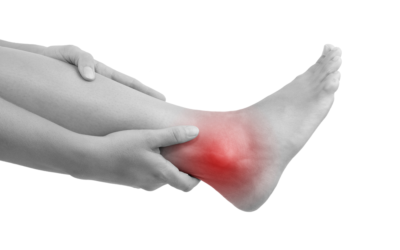

Ask a Foot Doctor: How Can You Tell If a Sprain Is Serious?

Each of our feet is made up of 26 bones, 30 joints, and over 100 muscles, tendons, and ligaments. With so many structures interacting when you walk, run, or jump, it's no wonder that the feet sometimes get injured, particularly when you participate in sports. While a...